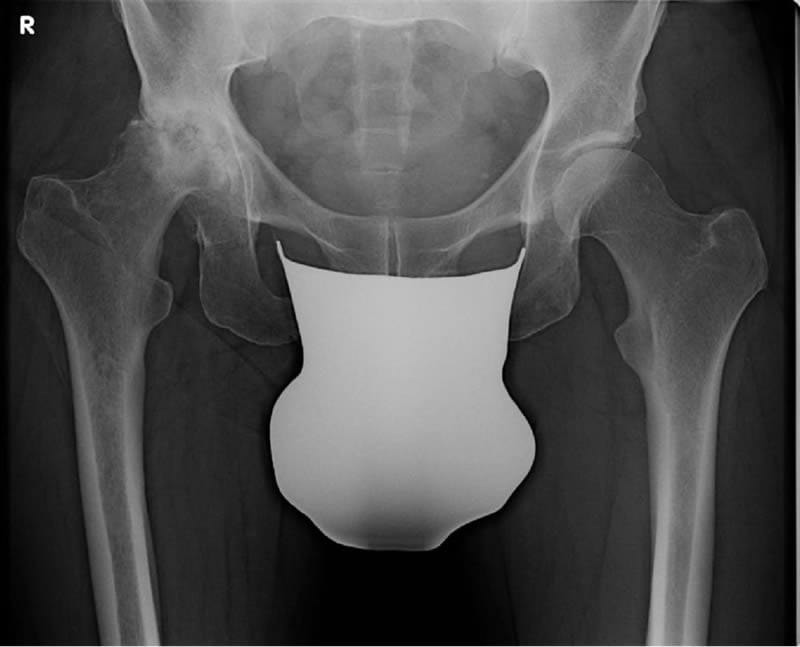

HüftTEP bei Coxarthrose klinische Leitlinie veröffentlicht